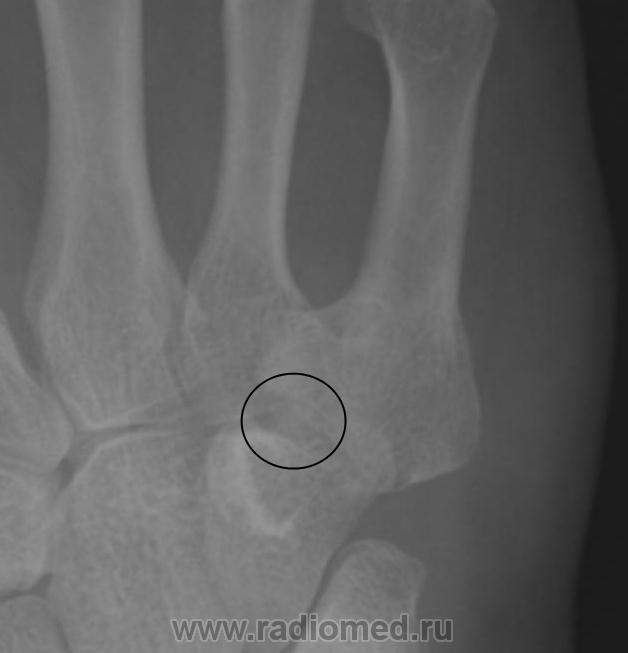

Точно такой-же локализации сесамовидных костей по Королюку не нашел, приблизительно такую локализацию имеет hamulus terminale(hamuli proprium, praesphenoid) №29 , но она там на много больше и вытянутая в проксимально-дистальном направлении. Так что склоняюсь к травматическому генезу этого образования.

Асептический некроз основания V пястной кости? Описывают же "раструбообразную деформацию" головки плюсневой кости при болезни Келлера, может быть здесь возникло нечто подобное. Костный фрагмент.